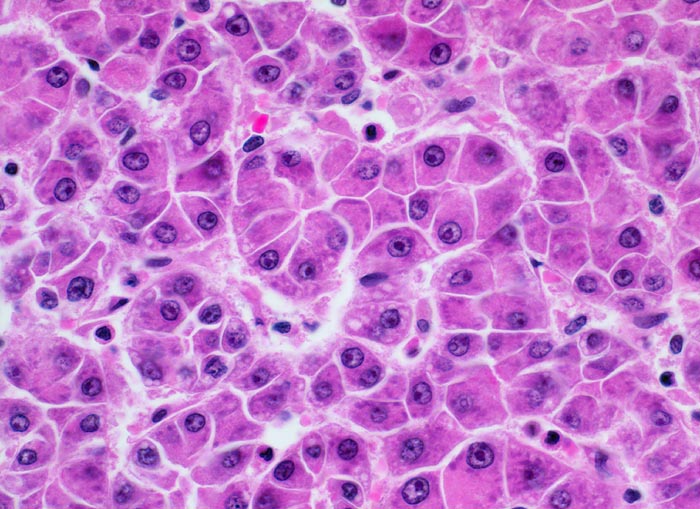

Makroskopisch imponiert das hepatozelluläre Karzinom als solitäre grosse Tumormasse, als zahlreiche zirrhoseartige Knoten oder als scharf begrenzter Knoten mit oder ohne Kapsel. Die tumorfreie Leber ist in der Mehrheit der Fälle zirrhotisch umgebaut. Mikroskopisch bilden die Tumorzellen mehr als 2 Zellen breite Trabekel (> 1237), kompakte Tumormassen (> 1229) oder pseudoglanduläre Strukturen (dilatierte Canaliculi) (> 1212) (> 1199). Desmoplastisches Bindegewebe fehlt meist. Innerhalb des Tumors fehlen Portalfelder. Es finden sich lediglich Arterien. Etwa bei der Hälfte der Karzinome lässt sich intrazytoplasmatische oder intracanaliculäre Galle (> 1238) nachweisen. Immunhistochemisch lassen sich mit einem polyklonalen Antikörper gegen Carcinoembryonales Antigen (CEA) Gallecanaliculi zwischen den Tumorzellen nachweisen. Die Tumorzellen bilden keinen Schleim.

• Die Tumorzellen bilden Trabekel, welche überwiegend mehr als 2 Zellen breit sind und Pseudodrüsen.

• Sinusoidartige Blutgefässe mit Endothelauskleidung verlaufen zwischen den Trabekeln und den Pseudodrüsen.

• Die Tumorzellen erinnern an normale Hepatozyten, sind aber kleiner als die Hepatozyten und die Kern-Zytoplasmarelation ist deutlich erhöht. Das Zytoplasma ist basophiler als das der angrenzenden Hepatozyten.

• Galle ist sichtbar in den Pseudodrüsen.